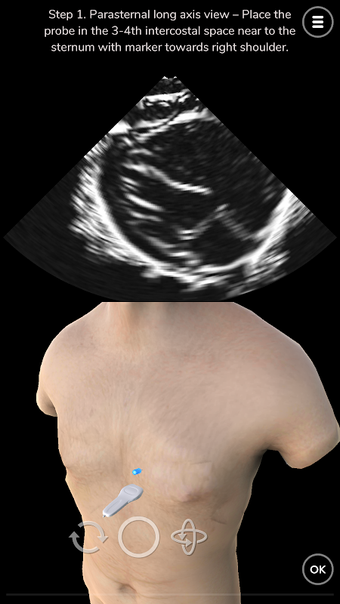

Deepscope Ultrasound Simulator est une application Android développée par Deepscope. Cette application gratuite est un module d'apprentissage virtuel créé pour aider les utilisateurs à apprendre les techniques de l'échographie. L'application est conçue pour être utilisée dans différents domaines médicaux tels que la médecine d'urgence (ER), la chirurgie, l'orthopédie, la rhumatologie, l'examen vasculaire, l'ophtalmologie et l'anesthésiologie. Elle peut même simuler l'échocardiographie et l'écho pour la cardiologie.

L'application couvre les mouvements de base de la sonde d'échographie ou de l'échographie, l'anatomie pertinente pour l'examen échographique, les techniques pour réaliser une échographie de l'aorte ou un examen échographique, les techniques pour réaliser une échocardiographie ou un écho, ainsi que les défis. Le simulateur d'échographie utilise des techniques avancées de graphisme informatique pour simuler les ondes sonores. Le résultat de ces simulations est un sonogramme.